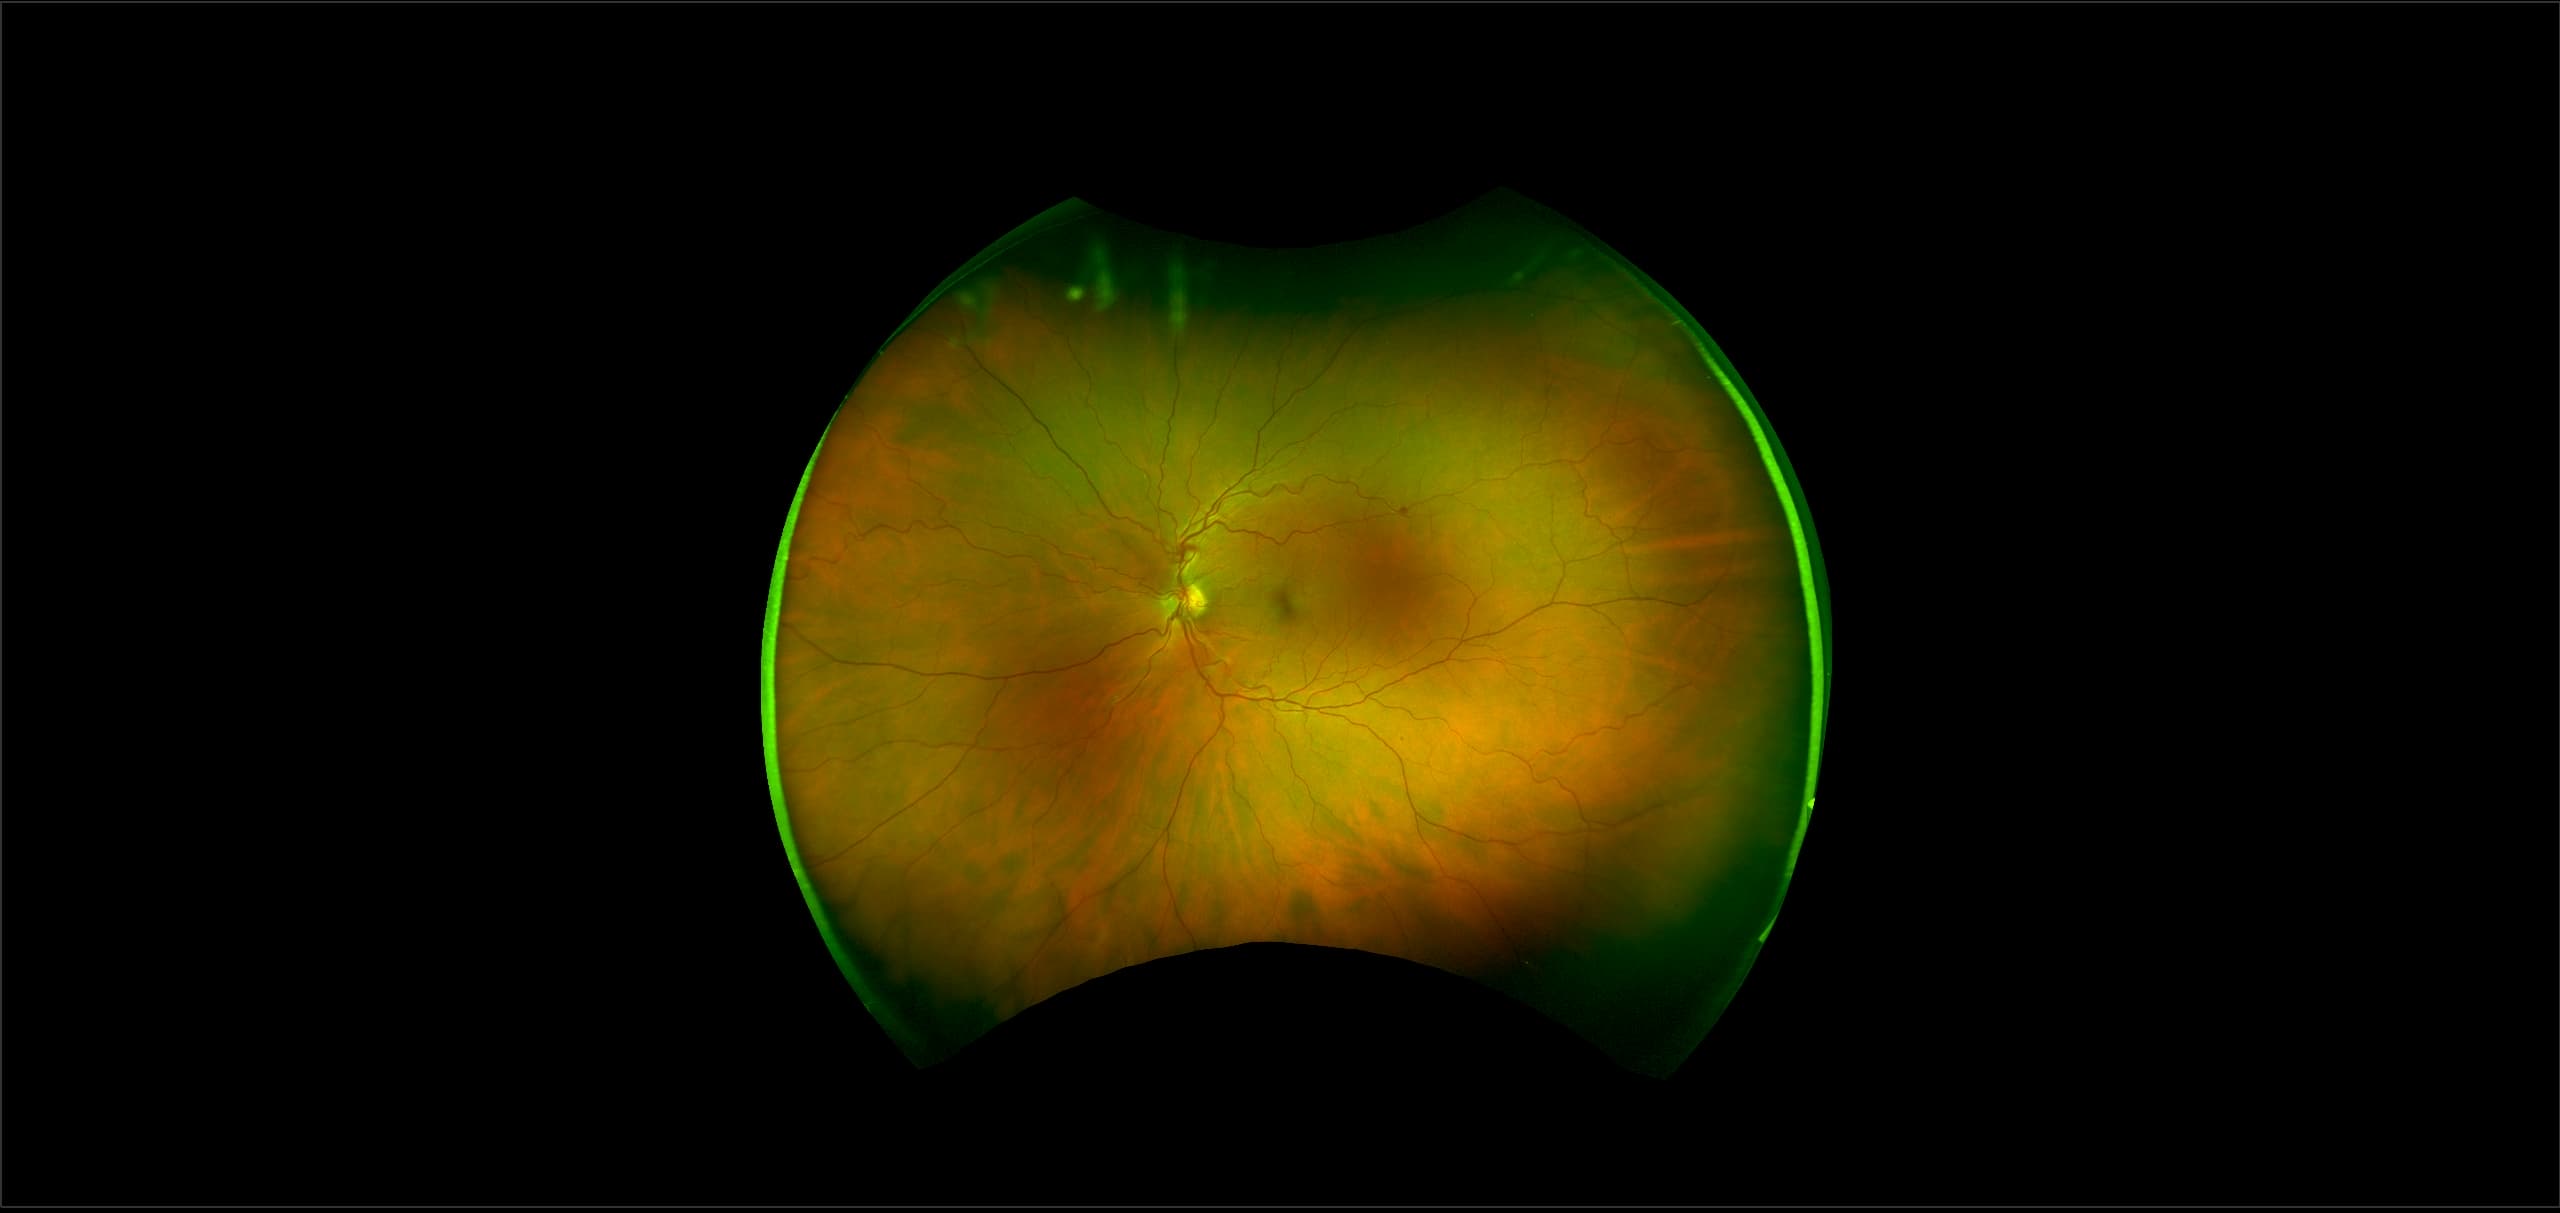

California - Large Pars Plana Cysts - Steered, RG

Pars plana cysts are a common peripheral retinal pathology that do not raise much clinical concern. They do not affect the central vision and observation alone is typically recommended. Pars plana cysts are something to be considered when peripheral retinal elevation is noted on routine exam.